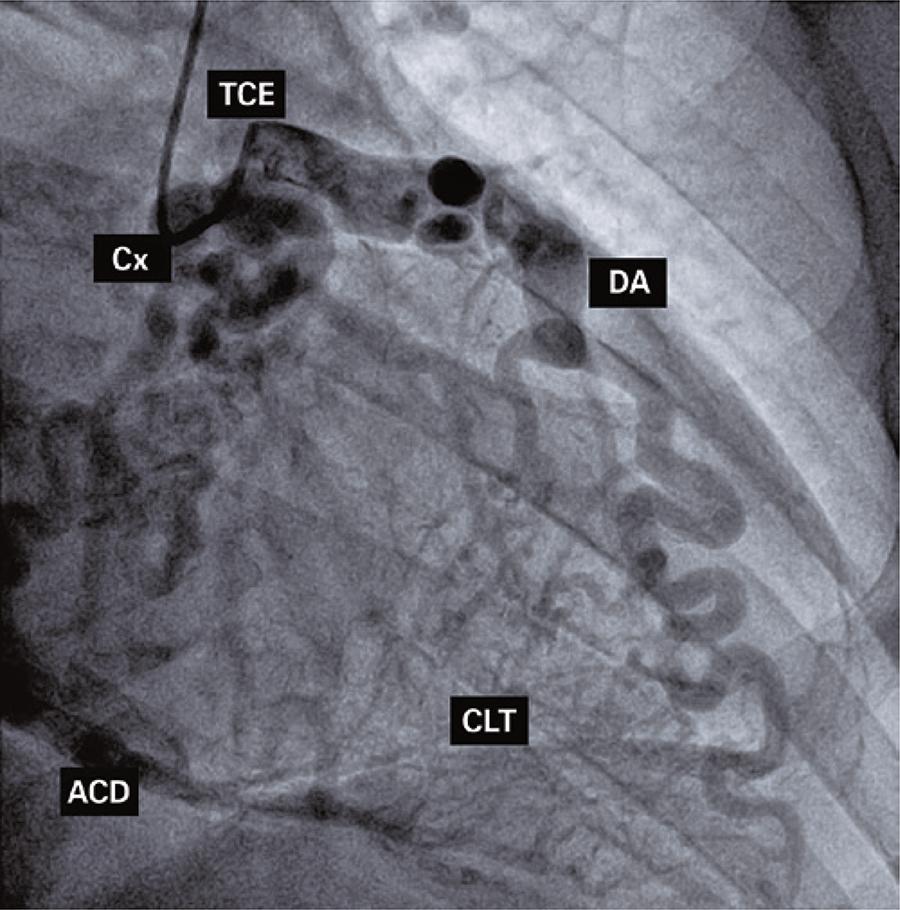

Artérias coronárias anômalas são patologias raras, especialmente quando a origem da artéria coronária direita se dá no tronco da artéria pulmonar. As manifestações da doença podem ocorrer precocemente, levando a morte súbita, infarto agudo do miocárdio ou cardiomiopatia isquêmica. Muitos casos descritos permanecem assintomáticos por longos períodos. A cirurgia é sempre indicada, como visto na maior parte da literatura. Descrevemos um caso angiográfico de um paciente de 76 anos, oligossintomático, encaminhado para cinecoronariografia eletiva para avaliação pré-operatória de cirurgia de próstata. Embora o tratamento cirúrgico seja a primeira escolha, especialmente no diagnóstico precoce, esse paciente foi referido para seguimento em tratamento conservador.